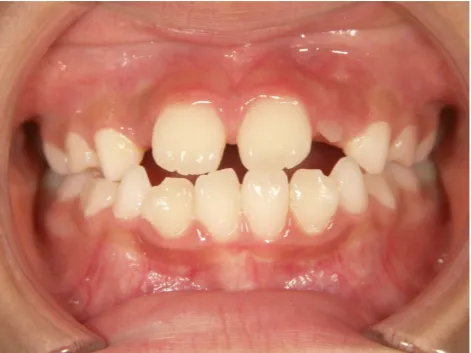

治療前①小2:8y1m 初診

| カウンセリング・診断結果 | 前歯が受け口になっていているため、適正な成長へ誘導するために前歯の咬み合わせの改善が必要なことを説明し、診断を希望されたので精密検査へ進みました。 精密検査の結果、骨格的には受け口傾向、下顎前歯の突出、上下ともアーチが小さく凸凹(叢生)が認められ、機能的には低位舌と口唇閉鎖不全があり、口元は上下唇とも突出していますがコンケーブになってないことがわかりました。 |